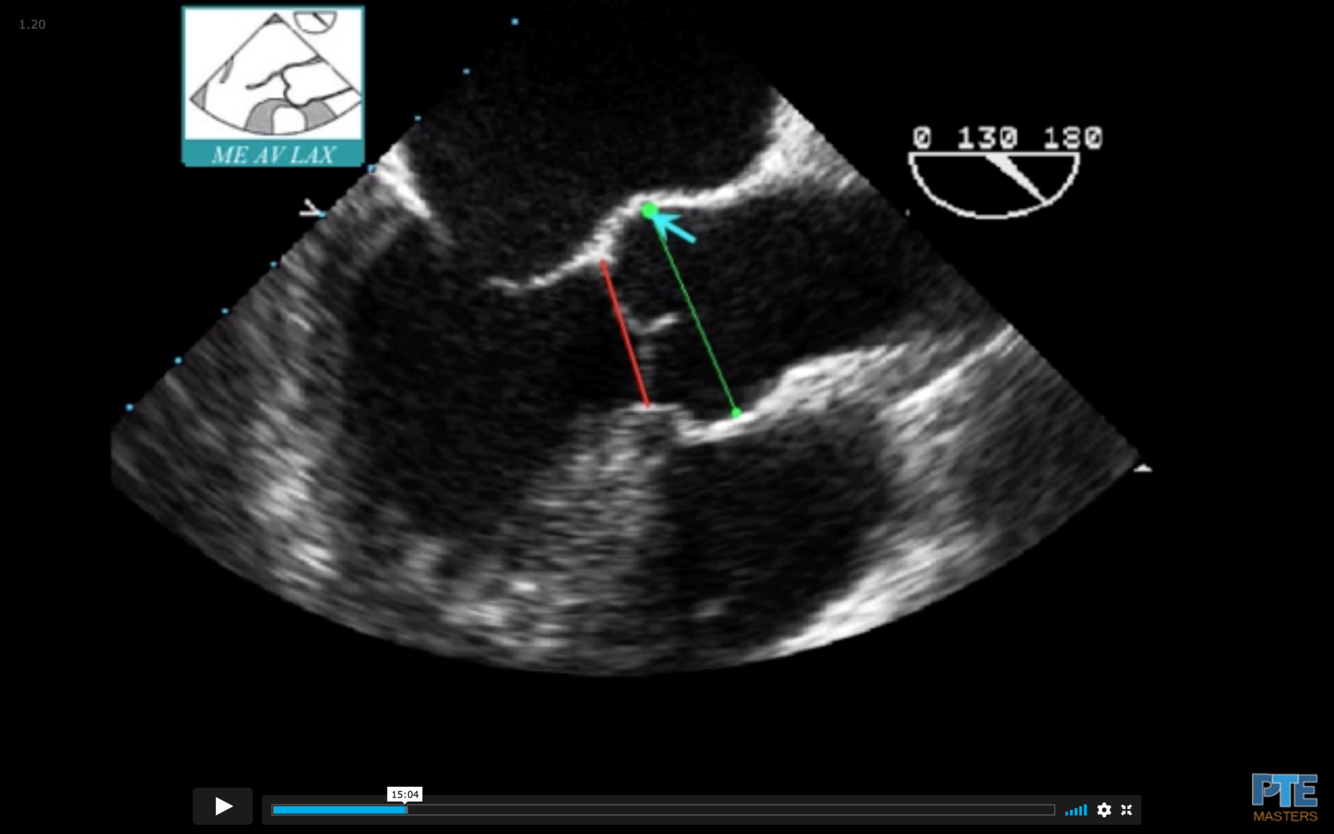

Annulus in red in the photo

Sinus of Valsalva is in Green

Junction in Teal